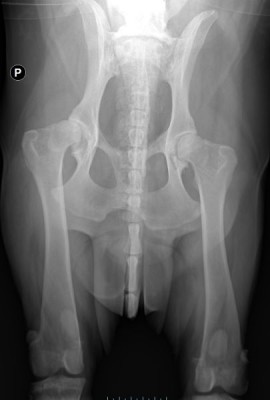

Na pierwszy rzut oka widać, że psiak ma znaczne problemy z poruszaniem się. Bamberek porusza się sztywno i stwierdzono u niego kulawiznę II stopnia na prawej tylnej łapce. Ma również widocznie osłabiony odruch korektury, zwiększone napięcie mięśni lędźwiowo-biodrowych, ograniczenie w odwodzeniu stawów biodrowych oraz obniżenie napięcia mięśniowego mięśni udowych. Na zdjęciach RTG widać u niego dysplazję stawów biodrowych, zmiany zwyrodnieniowe i stany zapalne, które z pewnością sprawiają mu ból :(

Niestety to nie koniec jego ortopedycznych problemów. W badaniu fizykalnym Pan doktor stwierdził zwiększoną bolesność odcinka lędźwiowo-szyjnego kręgosłupa. Na RTG kręgosłupa ma widoczne zmiany typowe dla zaawansowanej postaci zespołu końskiego ogona, zaawansowaną spondylazę a na domiar złego przewężenia w przestrzeniach międzykręgowych m.in. w odcinku szyjnym co ma wpływ na jego czucie (kwestie neurologiczne) i stanowi ryzyko paraliżu w przyszłości :(

Przednie łapki Bamberka są w tragicznym stanie. Ma on bardzo ograniczoną ruchomość, praktycznie nie może zgiąć łokci. Psiak cierpi na dysplazję łokciową i zaawansowaną artrozę stawów łokciowych (prawdopodobnie już jako kilkumiesięczny psiak nieprawidłowo stawiał te łapki ale jego „właścicielowi” pewnie przez myśl nie przeszło, żeby go diagnozować :( )

Miednica 2.jpg

Plik ściągnięto 11 raz(y) 20.63 KB

Miednica 1.jpg

Plik ściągnięto 8 raz(y) 33.76 KB